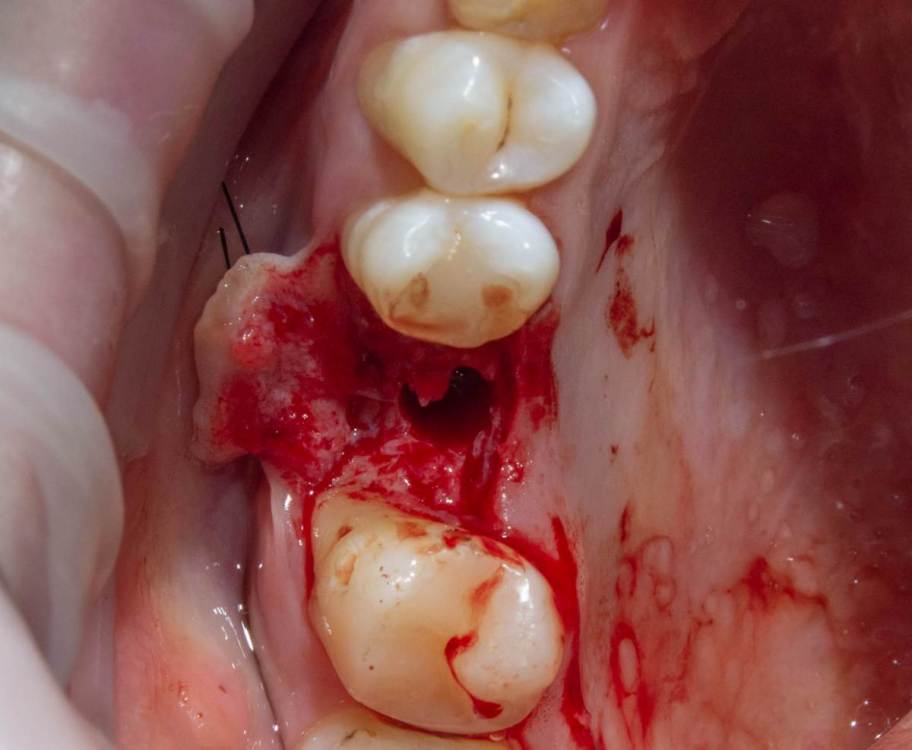

Женька Опубликовано 14 ноября, 2021 Автор Поделиться Опубликовано 14 ноября, 2021 Какой-то чудной зсл у меня получился... но это от недостатка опыта 100%. В общем фото сделал всего 2шт , скину в понедельник. Итак про ЗСЛ. Мой протокол: разрез, скелетирование, подшиваю лоскут для лучшей визуализации, далее пилотное дентиум не доходя 1-1.5мм, далее расширяю отверстие до нужного размера (здесь 3.8 имплантиум) и потом беру остеотом того же размера и стучим до появления "тупого" звука или ощущения "проваливания". Остеотомы у меня китайские, но со стоперами. Начинаю стучать и почти сразу чувствую, что провалился. Зондирую "зонтиком" - никакой эластичной подвижности... стучу ещё, тоже самое. Заметил, что стопер упирается проксимально в 2.7. Выкручиваю стоперы совсем. Стучу, звук особенно не меняется, но пациент отмечает неприятные ощущения. По остеотому 8мм (нативной кости 7 с копейками). Снова зондирую, снова не чувствую мембраны , пациент же говорит, что что-то есть, двигается будто. Решив, что хватит мучать бедолагу нарезаю пару столбиков Белкозина и пакую с помощью остеотома. Инсталирую имплантат и пациент отмечает чрезмерное распирание и легкую болезненность (еще 1.5 мм имплантата не погружено). Продолжаю глубить, всё спокойно. В итоге остановился на 1.5мм заглублении и заглушке, не рискнул ставить фдм, торк около 10). Вырезал сст, подшил вестибулярно и наконец-то закончил. Судя по РГ я подломил не только кортикальную пластинку, но и приличный кусок губки? Критично ли? После отметил лёгкую заложенность носа, без геморрагий. 4 Ссылка на комментарий

Женька Опубликовано 15 ноября, 2021 Автор Поделиться Опубликовано 15 ноября, 2021 Как и обещал... всего два фото... Когда-нибудь я буду всё успевать и делать нормальный интраоперационный фотопротокол) Ссылка на комментарий

Женька Опубликовано 19 ноября, 2021 Автор Поделиться Опубликовано 19 ноября, 2021 6 дней после... все разлетелось, еще и кровотечение на 5 день открылось, думается мне из-за швов. С нёба не снял ни одного шва. Первый раз такое, что через неделю в зоне имплантации швов почти не осталось у меня... при том, что натяжения не могло возникнуть ни откуда ведь (ну ок, отёк, но зона то маленькая). В прочем, контур слизистой вроде бы получилось восстановить. Уже думаю, а не купить ли вакуум формер и каппы делать, как Настя Смолякова. Ссылка на комментарий